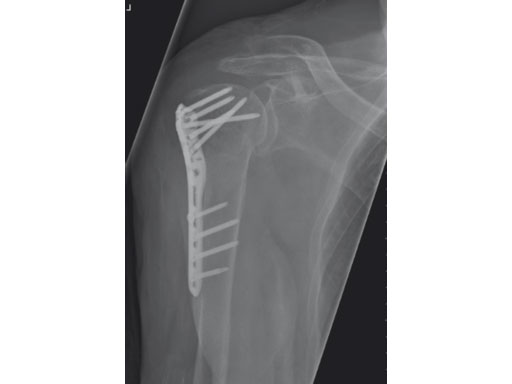

PHILOS is usually implanted through the deltopectoral approach which implicates a long incision and extensive soft-tissue retraction to reach the anatomy of interest. The less-invasive transdeltoid approach is more soft-tissue friendly and gives a better view of the greater tubercle.

The 3.5 mm LCP percutaneous aiming system for PHILOS offers the possibility to insert the PHILOS plate through the transdeltoid approach and to insert the shaft screws percutaneously enabling a less-invasive application of PHILOS.

A 76-year-old woman suffered a low-energy fall at home.